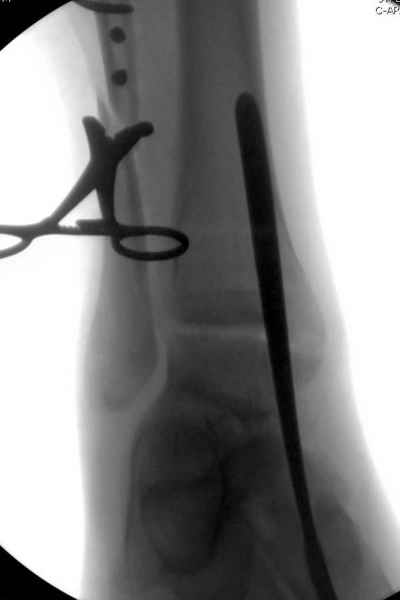

Мы бы, сблизив берцовые кости чрескожно наложенным репозиционным зажимом, провели позиционный межберцовый винт чуть ниже пластинки в положениий максимального тального сгибания стопы и ... на следующий день разрешили бы полностью наступать без гипса, брейса и т.п., но в обуви с небольшим каблуком 2-3 см и супинатором. Через месяц-полтора -винт удалить (если конечно не сломается).

Перелом типа Вебер С с эверсионным механизмом травмы всегда сопровождается повреждением дистального межберцового синдезмоза, поэтому вместе с фиксацией переломов лодыжек( малоберцовой кости) автоматом выполняется фиксация синдесмоза винтом, который обычно удаляется через 8 недель -

перед началом полной нагрузки на ногу.

Спустя 4 недели закрытая ( без отрытия зоны синдесмоза) репозиция может оказаться проблематичной, но все равно стоит попробовать из 1см разреза ввести тягловый винт и нтраоперационно проконтролировать межберц. синдесмоз. Предварительно стоит обсудить с больным вероятность открытия синдесмоза при безуспешности закрытой репозиции.

Здесь похожий случай трехнедельной давности, перелом почти сросся и была укорочена малоберцовая, на операции длину малоберцовой смогли восстановить только после того, когда проксимальнее пластины ввели шуруп и использовали его как толкатель, с помощбю дистракционого инструмента (lamina spreader).